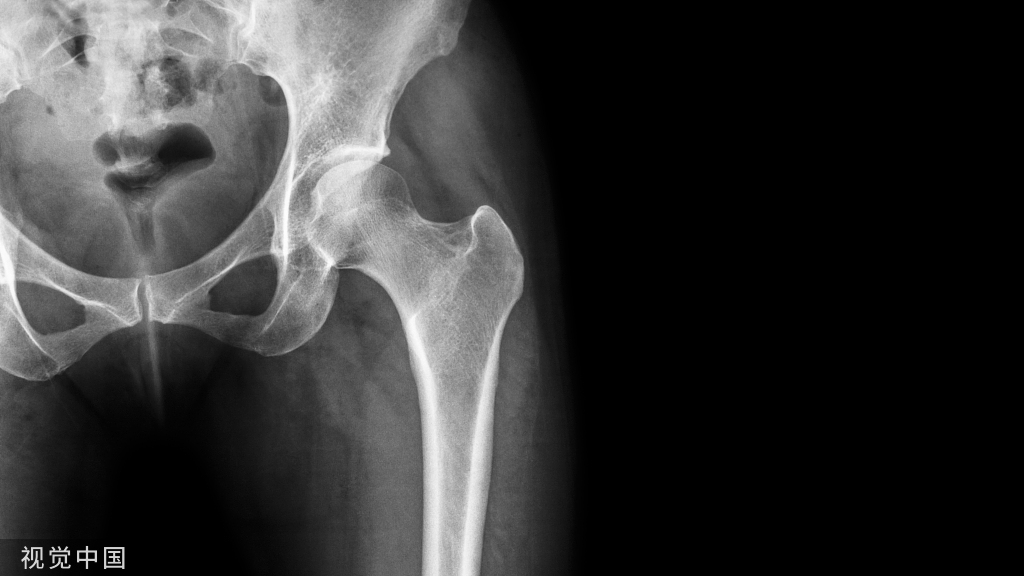

颈椎病X线片特征